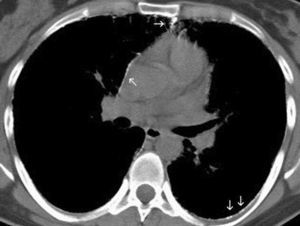

Las imágenes demostraron la presencia de puntiformes y difusas calcificaciones bilaterales, de predominio subpleural, en pleura mediastínica y en los septos interlobulillares. Los segmentos posteriores e inferiores estaban mayoritariamente afectos (fig. 2). También se visualizaron nódulos calcificados a nivel de segmentos anteriores (fig. 2B). El estudio detallado de alta resolución demostró un "patrón en empedrado" o crazzy-paving con marcado engrosamiento de los septos interlobulillares asociado a áreas parcheadas de aumento de la densidad en "vidrio deslustrado" o ground-glass, con mayor afectación de los segmentos posterobasales (figs. 3A y B). A nivel de los lóbulos superiores también se evidencian pequeños quistes subpleurales (fig. 3C).

Fig. 2. Corte axial de tomografía computarizada torácica convencional con ventana de mediastino. (A) Se evidencia la presencia de múltiples calcificaciones puntiformes localizadas en mediastino anterior, pleura mediastínica y en el espacio subpleural posterior. En cortes axiales inferiores (B) se observa además moderado engrosamiento de los septos interlobulares con finas calcificaciones, y con mayor predisposición de los segmentos posteriores, así como nódulo calcificado anterior (flecha).